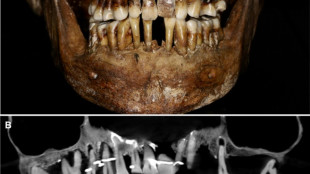

Scientists have discovered the long-buried secret of a 17th-century French aristocrat 400 years after her death: she was using gold wire to keep her teeth from falling out.